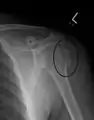

| Humerus fracture | |

| Midshaft humerus fracture with callus formation | |